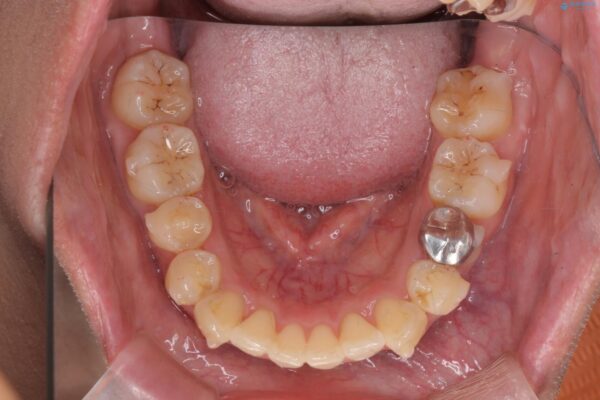

前歯のガタつきの改善を主訴にご来院されました。 特に犬歯の傾きが気になるとのことでした。

犬歯がかなり手前に傾いていましたが、ガタつきはそれほど強くないため非抜歯でマウスピース矯正が可能と判断しました。

治療前

気になる犬歯のガタつきをマウスピース矯正で改善 治療前画像 気になる犬歯のガタつきをマウスピース矯正で改善 治療前画像 気になる犬歯のガタつきをマウスピース矯正で改善 治療前画像 気になる犬歯のガタつきをマウスピース矯正で改善 治療前画像